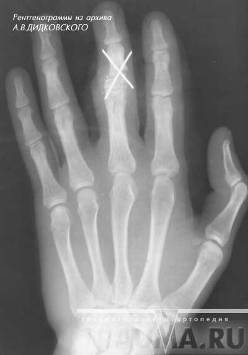

При переломах фаланг наблюдаются обычные признаки переломов костей: припухлость и кровоизлияние в области перелома, наличие деформаций, болезненность при пальпации области перелома и нарушение функции поврежденного пальца. Все эти признаки имеются при смещении отломков. Выраженная деформация отсутствует при переломах без смещения (рис.6, 7), трещинах и внутрисуставных повреждениях (9, с.89).

Рисунок 6 - Внутрисуставной перелом средней фаланги пальца.

Рисунок 7 - Перелом основной фаланги ІІ пальца (а) и двойной перелом (б).